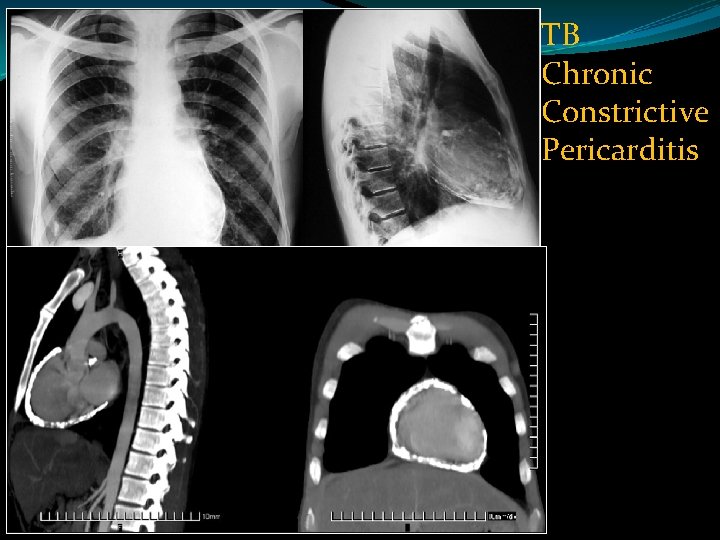

TB Chronic Constrictive Pericarditis

CT volume rendered image : dense egg-shell calcification of the pericardial mimicking "snow fall on mountain"